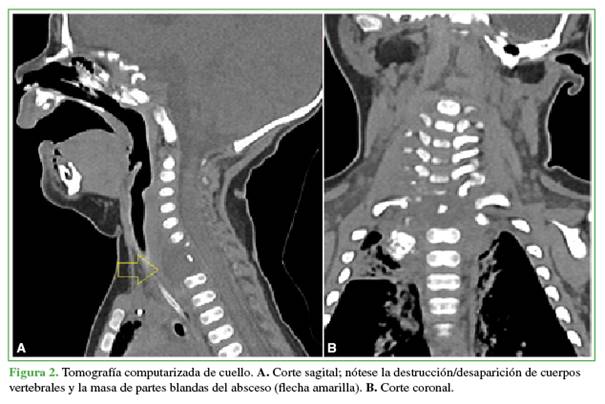

El cuadro respiratorio continuó deteriorándose por lo que se realizó una tomografía computarizada helicoidal con reconstrucción (Figura 2).

Se visualizó un importante absceso retrofaríngeo y retrotraqueal, asociado a osteólisis de los cuerpos vertebrales cervicales inferiores, con lesión de tipo infeccioso en el raquis cervical inferior y torácico superior. Para completar la evaluación se solicitó una resonancia magnética que confirmó el absceso y la destrucción infecciosa de los cuerpos vertebrales de T1, C7 y C6 (este último parcialmente) (Figura 3).

Si bien la ecografía y la radiología convencional pueden ser de alguna utilidad para el diagnóstico de esta enfermedad, la resonancia magnética de columna es el estudio diagnóstico de elección por su mayor sensibilidad y especificidad. Permite evaluar y diferenciar la destrucción ósea y discal, y delimitar la existencia de abscesos paravertebrales.12 En nuestro caso, el uso de la tomografía computarizada antes de la resonancia se debió a la disponibilidad en la institución; sin embargo, fue muy útil para mostrar la lesión y evaluar la destrucción ósea (Figura 2).